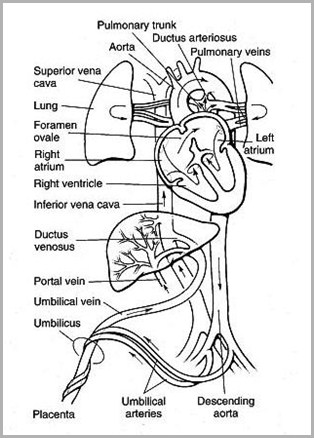

Placenta umbilical vein(ligamentum teres) hepatic sinusoid & ductusvenosus (ligamentumvenosum) portal vein IVC right atrium foramen ovale leftatrium left ventricle aorta systemiccirculation umbilicalarteries placenta

Fetal Circulation

From the umbilicus,umbilical vein passescephalad, slightly toright

Joins the left branch ofthe portal vein

The ductus venosusarises from the pointwhere the UV joins theleft portal vein

Ductus venosus entersIVC

UVC should be justabove diaphragm whereIVC enters RA (T8-T9)

Umbilical arteriesare directcontinuation ofinternal iliacarteries

UAC will usuallyenter aorta viainternal iliac artery

UAC should thenpass up aorta,above diaphragm,between T6 and T9